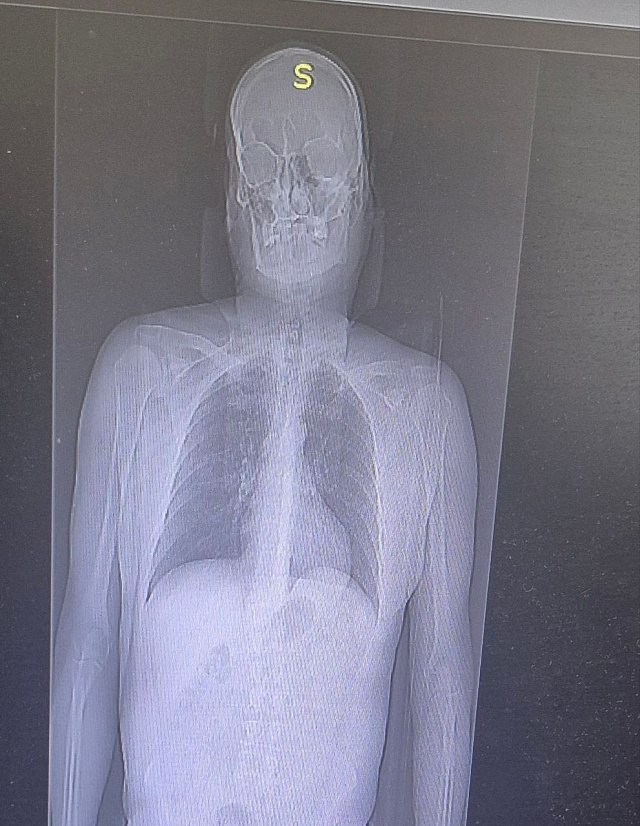

По результатам обследований у мужчины диагностировали переломы двух ребер и ушибы мягких тканей. Состояние пациента стабилизировали. Уже на следующей неделе он будет готовиться к выписке.